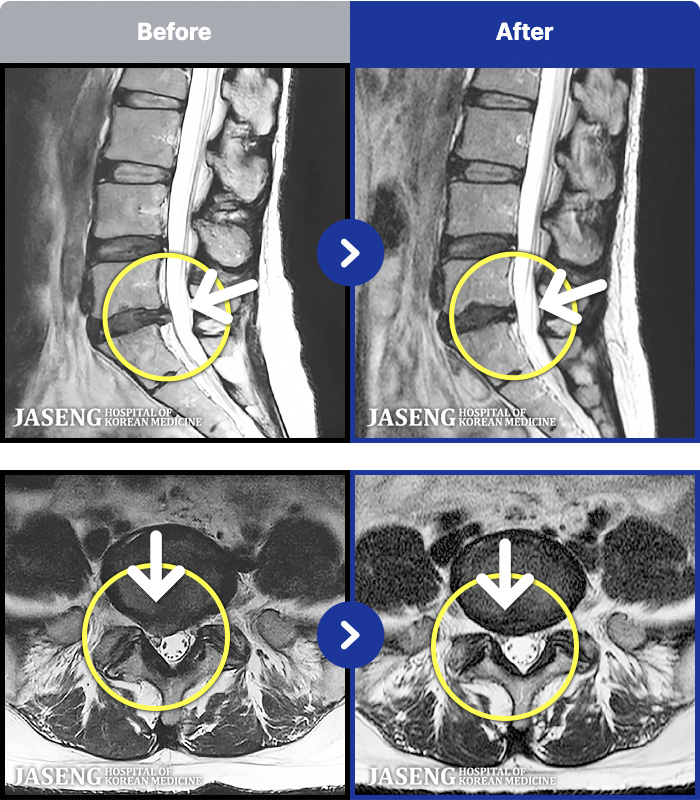

1,241 MRI ũ ʸ Ȯϼ.

㸮, ٸ ٷ

ǿ

ȯ

㸮ũ

[Կñ:03.04.01~09.11.01]

[_㸮ũ] 㸮 , ٸ ̾ ϼ̽ϴ.

No.1236

ȸ 4,693

2025.09.22